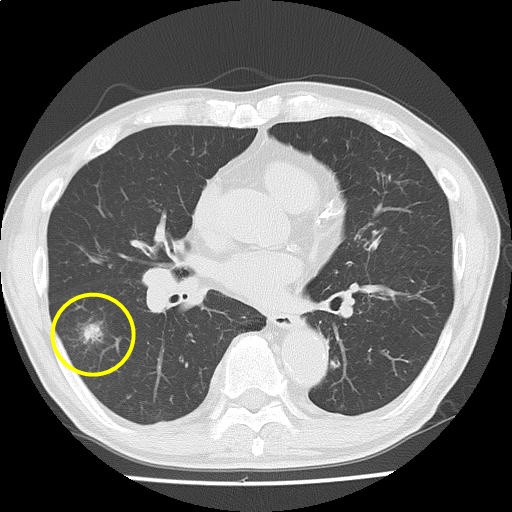

【画像診断検査結果】

(Findings)

肺野に気腫性変化を認める。

気管支壁肥厚はやや増悪。右肺優位に粒状影およびすりガラス影〜コンソリデーションの出現を認め、気管支肺炎を疑うが、 右下葉に一部腫瘤様にみえる所見あり、経過観察を要する。

縦隔リンパ節腫大を認めるが、炎症性反応と考える。

胸水は認めない。

(Impression)

s/o 気管支肺炎

CT画像10

(34/221)